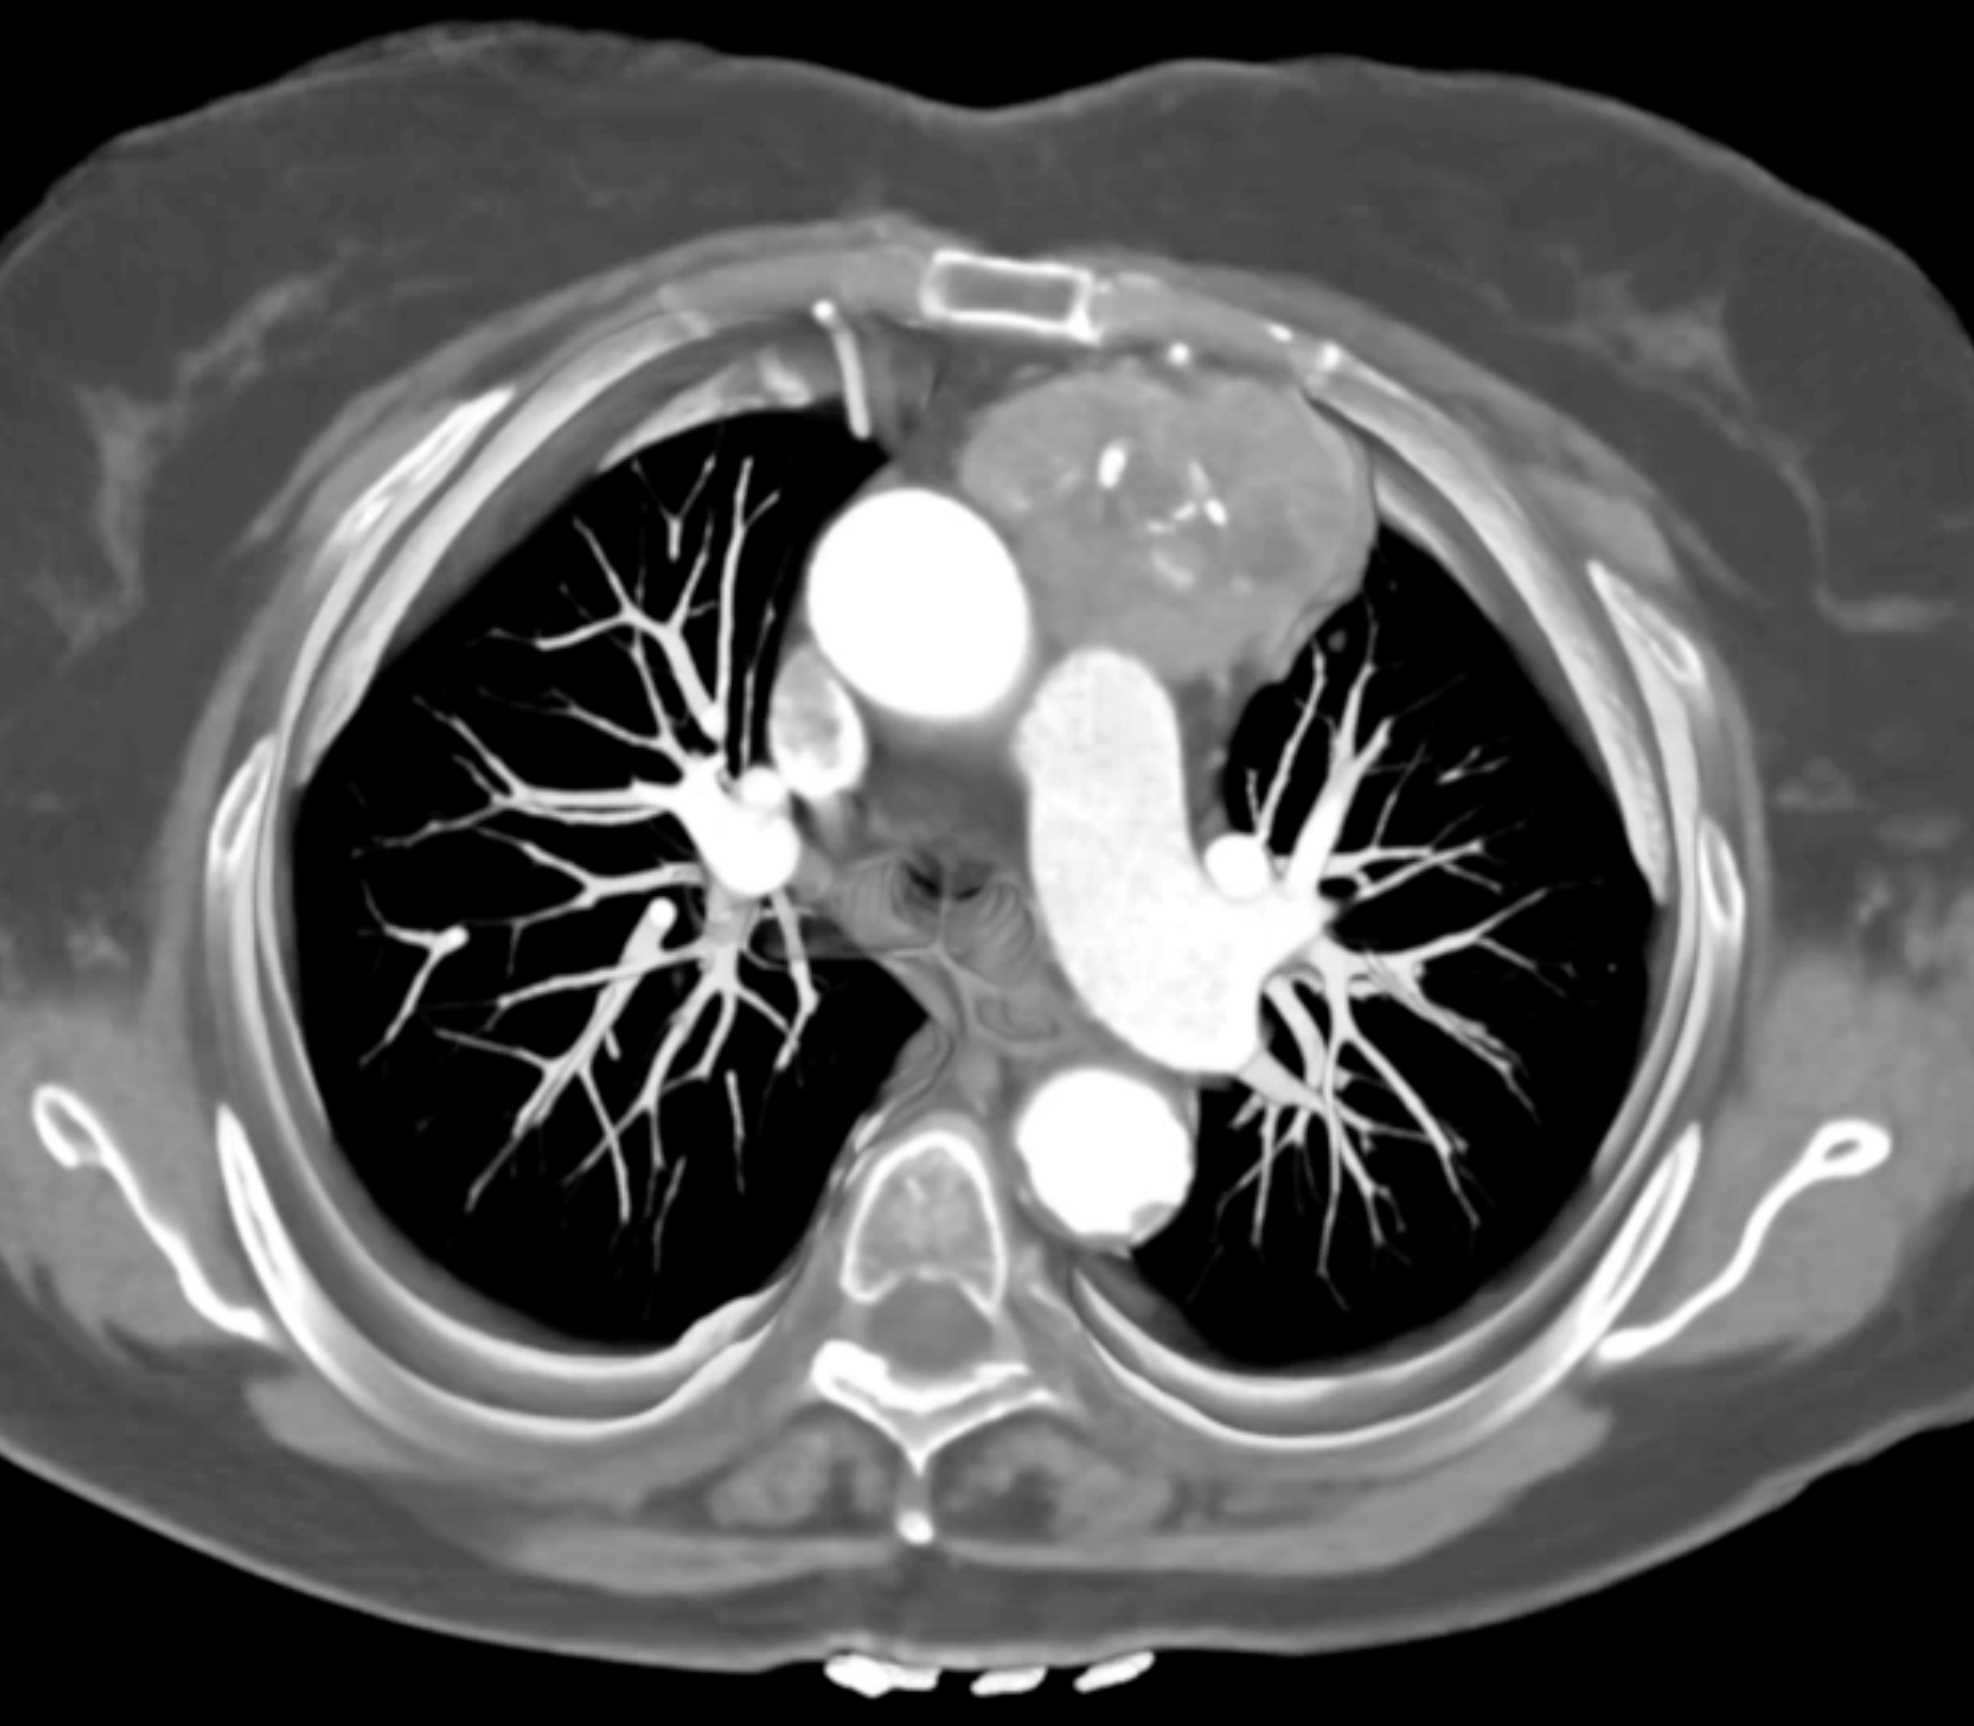

Thymic Carcinoma